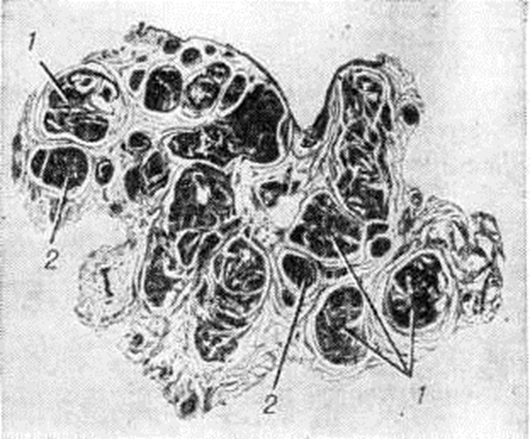

Дефицит фактора XI (синонимы: гемофилия С, дефицит предшественника тромбопластина плазмы, синдром Розенталя) впервые описали в 1953 г. Розенталь (R. L. Rosenthal), Дрескин и Розенталь (О. Н. Dreskin, N. Rosenthal). В последующие 10 лет было описано св. 120 больных во всех частях света, однако статистических данных о распространённости дефицита фактора XI нет. Наследуется по аутосомно-доминантному типу с неполной пенетрацией гена; не исключается и аутосомнорецессивный характер наследования. Обнаруживается у лиц обоего пола с одинаковой частотой. Фактор XI — предшественник тромбопластина плазмы, активизируется под действием активного фактора XII, способствует превращению фактора IX в активную форму; при недостаточности его нарушается образование тромбопластина. Это белок, при электрофорезе мигрирует в зоне β2глобулинов. Стабилен при хранении, не потребляется в процессе свёртывания крови. Место синтеза не установлено. При хронический действии этих факторов развивается гиперплазия кавернозных телец, они увеличиваются в объёме, стенки их утолщаются и таким образом формируется геморроидальный узел. Повреждение поверхностно расположенных кавернозных вен геморроидальных узлов во время дефекации приводит к возникновению главного симптома Геморой — ректальных кровотечений, имеющих, как правило, артериальный характер. Это подтверждается клиникой (выделение алой крови напряжёнными каплями или даже пульсирующей струйкой) и исследованием газового состава крови, взятой непосредственно из узла. Патологическая анатомияКавернозные вены прямой кишки при Геморой постепенно увеличиваются, принимают вид покрытого слизистой оболочкой узла на широкой ножке, свисают в просвет кишки и могут выпадать из анального отверстия. Стенки таких узлов истончены, нередко изъязвлены или аррозированы. При микроскопическом исследовании удалённых геморроидальных узлов обнаруживается гиперплазия кавернозных телец [Штельцнер (F. Stelzner), 1963]. Стенки кавернозных вен утолщены, склерозированы, число артериовенозных анастомозов в них возрастает, просвет их расширяется (рисунок 1—3).